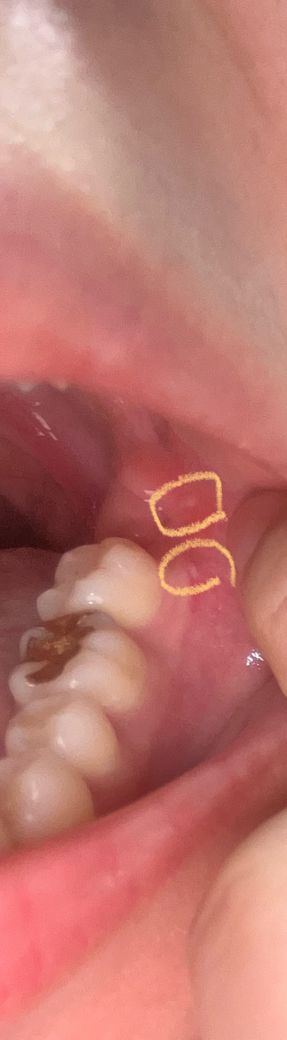

잇몸 물혹인가요? 생긴지 한달 넘은것같은데.. 잇몸 물혹이라면 발치해야하는건가요?

생긴지는 한달 넘었습니다 이게 뭘까요 ? 잇몸 물혹인가요 한달전쯤 치과가서 사랑니때문에 엑스레이 찍었었는데 별말이 없으셨어요 한곳은 사랑니뺀 쪽이에요 사랑니 발치 2주정도 넘은 후에 생긴것같아요 그때는 지금보다 더 작긴했는데 20대인데 임플란트해야하는걸까요?

잇몸이 자극을 받아서 단순 수포가 생긴거 같습니다. 큰 문제가 잇는건 아니니 너무 걱정하지마세요.

사랑니를 발치했다면 사랑니를 발치한 후에 치아를 수복할 필요는 없습니다. 사진으로 보이는 잇몸의 증상은 크게 문제가 되는 것으로 보이진 않습니다. 해당 부위가 불편하거나 걱정이 되신다면 치과에서 진료를 받아보는 것을 권유드립니다.

2. 걱정하시는 부분은 그 옆 두번째 큰 어금니일텐데 제가 보기엔 치아 문제 때문에 생긴 염증 양상은 아닙니다.

3. 단순 구내염일 가능성이 높으나 한달이상 지속되었다면 구강내과를 가보시는 것도 추천드립니다.